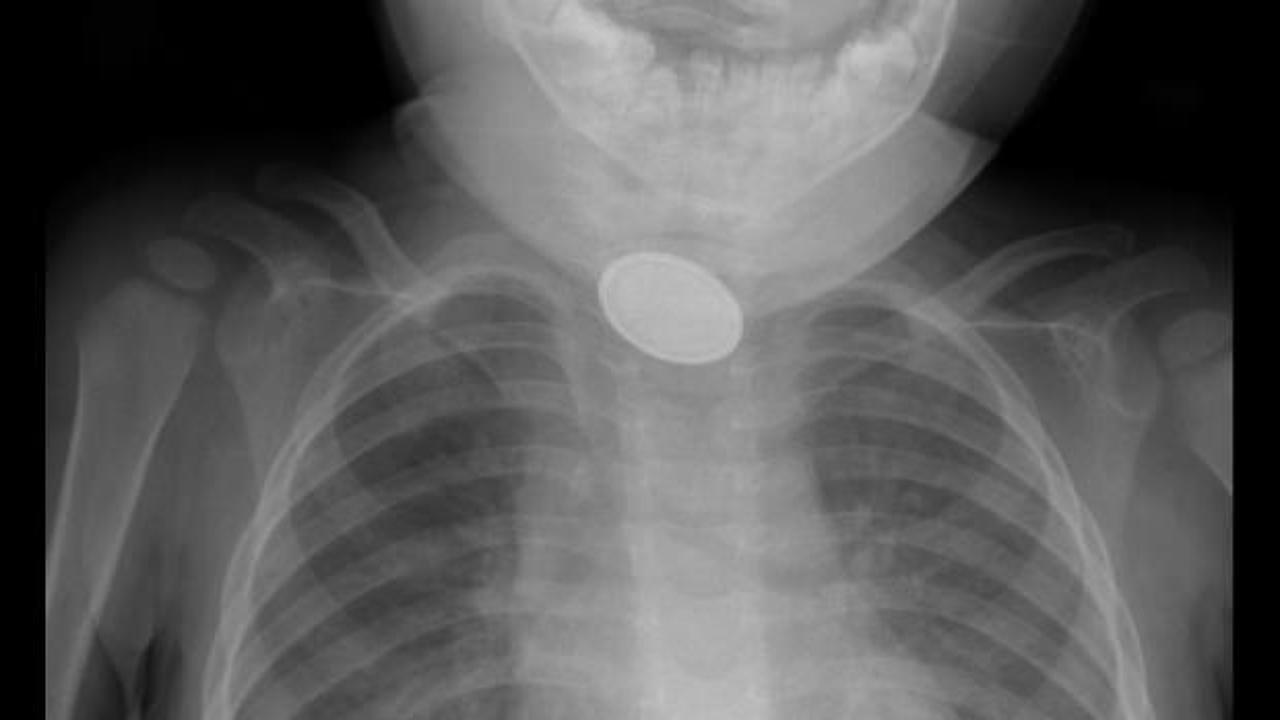

Kayseri’de 15 aylık A.Y.Ç.’nin yemek borusuna, evde oyun oynadığı sırada düğme pil ve lego oyuncak parçası kaçtı. O sırada yanında olan 4 yaşındaki kardeşi, ‘Kardeşim lego yuttu’ diyerek annesini çağırdı. A.Y.Ç.’nin ağızına bakan anne Tuğba Yılmaz, parçayı göremeyince dışkısından çıkacağını düşündü. Bir süre sonra A.Y.Ç.’nin yutma güçlüğü çektiğini gören Tuğba Yılmaz, Kayseri Şehir Hastanesi’ne başvurdu. A.Y.Ç.’ye yapılan röntgende, yemek borusunda düğme pil ve lego parçası oyuncağa rastlandı. Kız bebek A.Y.Ç., Kayseri Şehir Hastanesi Çocuk Cerrahisi ve Ürolojisi Anabilim Dalı Başkanı Doç. Dr. Mustafa Erman Dörterler ve ekibi tarafından ameliyata alındı. Yaklaşık 3 saatlik süren operasyonun ardından A.Y.Ç.’nin yemek borusuna kaçan düğme pil ile lego oyuncak parçası çıkarıldı.

Kayseri Şehir Hastanesi Çocuk Cerrahisi ve Ürolojisi Anabilim Dalı Başkanı Doç. Dr. Mustafa Erman Dörterler, “Hastamız 15 aylık bir bebek. Hastamız, disk pil ve beraberinde bir lego parçası yutmuş. Ben gece 01.30 gibi hastaneye geldim. Pili ve lego parçasını yutmasının üzerinden yaklaşık 6-7 saat geçmişti. Bu durumlarda dakika ve zaman çok önemli. 2 saatten sonra çok ciddi sıkıntılar oluşturabilecek hatta ölümle sonuçlanabilecek durumlarla karşı karşıya kalmaktayız. Ben, göğüs cerrahisi, çocuk gastroenteroloji, anestezi ekibi ve yardımcı sağlık personelleriyle beraber yaklaşık 20-25 kişiydik. Çocuğa, hızlı ve dikkatli bir şekilde müdahale ettik. Çünkü zaman ilerlediği için disk pil, yemek borusuna yapışmış ve delmek üzereydi. Dikkatli şekilde özenerek çıkarmaya çalıştık. Ekip çalışmasıyla beraber çıkarmayı başarabildik. Çocuğumuzun yoğun bakımdaki 2 günlük takip süreci devam ettikten sonra servisimize aldık. Şu an gayet iyi” diye konuştu.